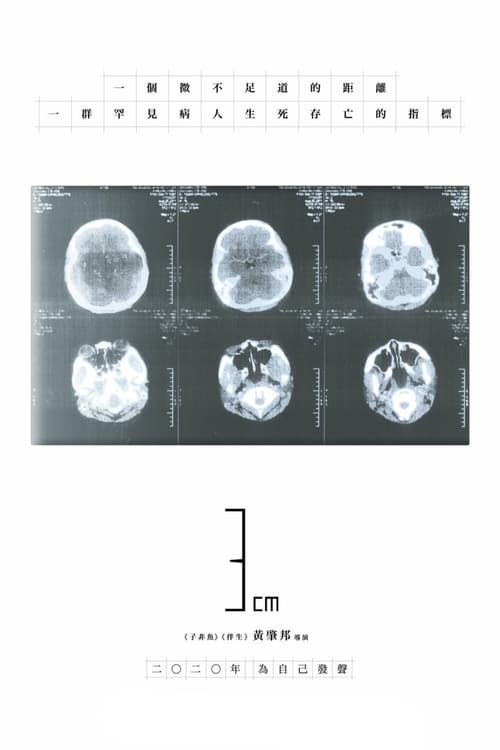

3cm

Tuberous Sclerosis Complex (TSC) is a genetic disorder that causes noncancerous tumors to grow in different parts of the body. However, the Hong Kong government has been slow to allow treatment for the disease, especially in relaxing regulations for drugs that treat the tumors. Director Wong Siu-pong turns his camera on Hong Kong’s medical system with this heartrending documentary about a young TSC patient who also lost her mother to the disease.